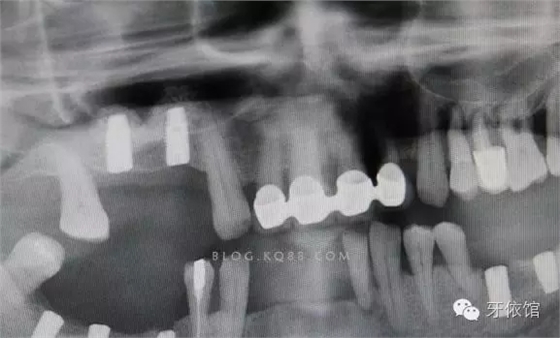

再用CAS鉆鉆透另一個(gè)窩洞的竇底,此時(shí)如果兩個(gè)窩洞離得近,那么第二個(gè)窩洞竇膜通過提升第一個(gè)窩洞竇膜時(shí)就已經(jīng)被提起了(不絕對(duì),這個(gè)病例就沒有被提起來,通過最后的X光片可以看到)。

再次對(duì)第二個(gè)窩洞進(jìn)行水壓沖頂,如果膜沒有破裂,且兩個(gè)窩洞之間沒有上頜竇間隔,在第二個(gè)洞注水時(shí)水會(huì)從第一個(gè)洞流出生理鹽水。

通過鼓鼻法檢查,判定上頜竇膜完好。